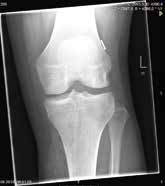

Das vordere Kreuzband ist ein zentraler Pfeiler des Kniegelenkes. Die Ruptur der Kreuzbänder zählt zu den häufigsten traumatischen Bandverletzungen im Sport (Abb. 1). 70 % der Kreuzbandrupturen ereignen sich zwischen dem 15. und dem 45. Lebensjahr. Frauen haben ein 2,3- bis 9,7‑fach erhöhtes Risiko gegenüber Männern 1. Sportler in Sportarten mit Sprüngen und plötzlichen Richtungswechseln (Ballsportarten, Ski alpin etc.) sowie Kampfsportarten (Ringen, Judo etc.) sind besonders gefährdet.

Bei der projektionsradiographischen Untersuchung des Kniegelenkes a. p. und seitlich können knöcherne Kreuzbandausrisse diagnostiziert werden. Um die Pathomorphologie der Kreuzbandverletzungen und Begleitverletzungen zu objektivieren, wird in der Regel eine MRT-Abklärung erfolgen.